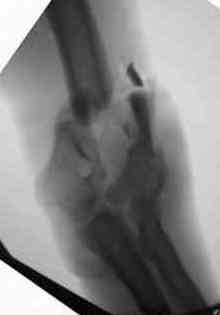

Во втором случае у пациента с открытым многооскольчатым переломом дистального плеча на 4 сутки выполнен остеосинтез. Обратите внимание =доступ без резекции олекранона,медленная и ювелирная работа нетипичным для нас инструментом закончена полным восстановлением анатомии локтевого сустава.В небольшой дефект залит БМП\OP-1 Stryker ,продукт роста клеток человека в генной модификации\. Для профилактики гетеротопической оссификации ряд врачей применяют облучение на 2-3 сутки .Предвижу реплики скептиков - нам бы их зарплаты и оснащение, мы бы!